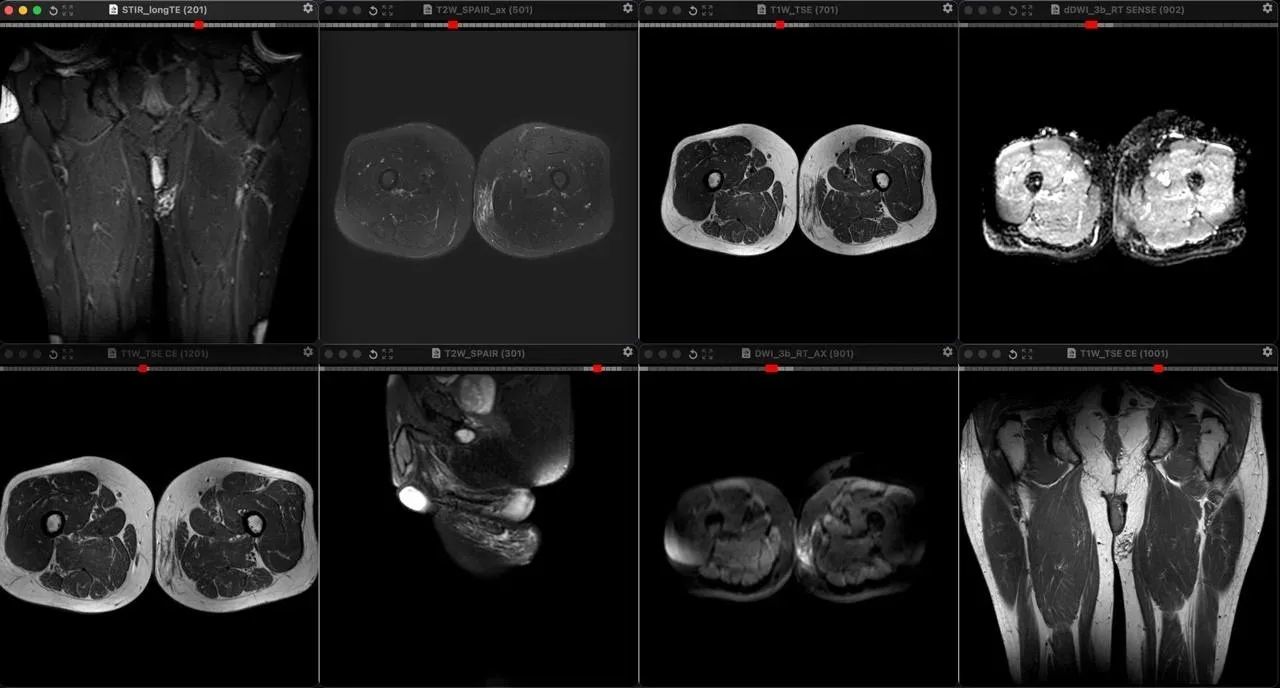

Плексиформная кожная нейрофиброма у мужчины 34 лет с известным диагнозом Нейрофиброматоз первого типа. В отличие от типичных мишеневидных поражений, идущих вдоль крупных нервов при глубоких плексиформных нейрофибромах, поверхностные плексиформные нейрофибромы при НФ1, как правило, асимметричны, имеют немишеневидную структуру, не обладают узловатой или фасцикулярной морфологией и поражают кожу, а не только клетчатку. У этого пациента, как он говорит, шишка на внутренней поверхности левого бедра в течение многих лет, не меняется.